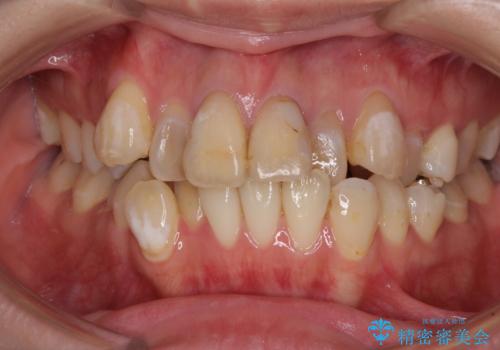

気になる八重歯と変色した前歯 抜歯矯正とセラミッククラウン治療